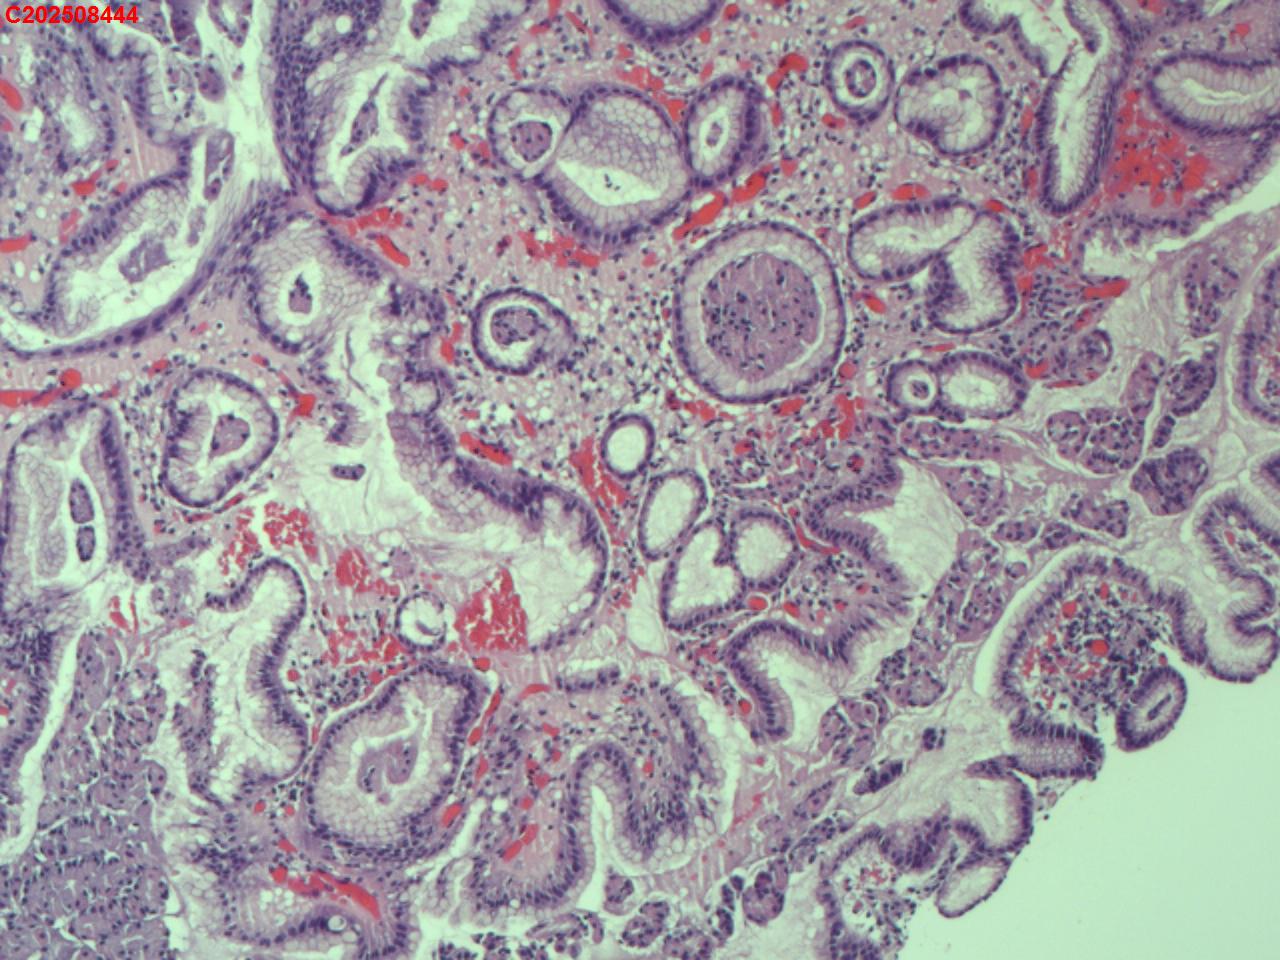

胃体可见多发直径2mm息肉,稍隆起,圆丘形

图2

增生性息肉

符合增生性息肉。

固有层粉染的是免疫球蛋白吗?